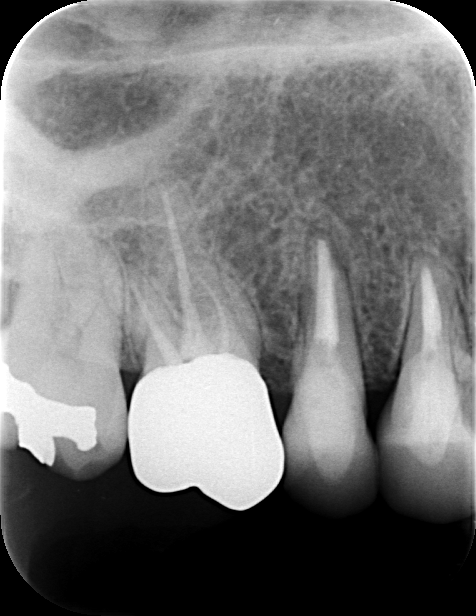

術後の検診でも順調に治癒が進み、約3ヶ月後には上部構造(人工の歯)を

装着することができました。通常の治療法であれば6〜9ヶ月かかるところを、

半分の期間で治療を完了できたのです。

4が月で治療終了

3ヶ月で完了:時間も大切な価値

この患者さんの場合、わずか3ヶ月で治療が完了しました。